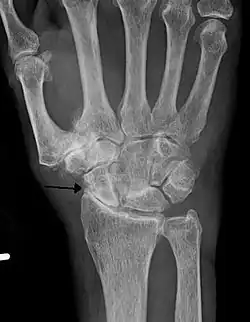

Lateral X-ray scan of ankle with secondary osteoarthritis

Lateral

Frontal X-ray scan of ankle with secondary osteoarthritis

Frontal

Secondary osteoarthritis of the ankle (due to an old bone fracture) in an 82-year-old woman

X-ray of erosive osteoarthritis of the fingers, also zooming in on two joints with the typical "gull-wing" appearance

Both primary generalized nodal osteoarthritis and erosive osteoarthritis (EOA, also called inflammatory osteoarthritis) are subsets of primary osteoarthritis. EOA is a much less common and more aggressive inflammatory form of osteoarthritis, which often affects the distal interphalangeal joints of the hand and has characteristic articular erosive changes on X-ray.[60]